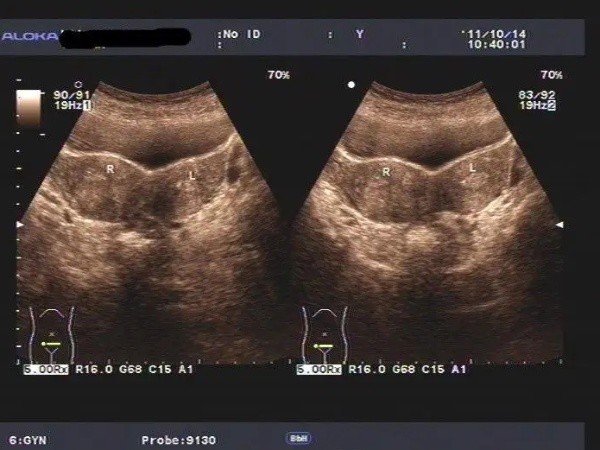

通过b超是能检查出女性子宫畸形,一般女性子宫畸形的类型有很多,如纵隔子宫、马鞍形子宫、鞍弓形子宫、单角子宫、双角子宫等,基本上通过B超就能清楚的检查出来。但毕竟每个女性的身体情况不同,子宫畸形的类型也不同,有部分子宫畸形就要通过宫腔镜检查、磁共振成像检查、CT检查或者子宫输卵管造影术检查等才能查出了。下图是子宫畸形B超图片:

子宫畸形又称子宫发育异常,是一种先天性疾患也是生殖器官畸形中最常见的一种。有些子宫畸形患者可能没有任何自觉症状,月经、性生活、妊娠、分娩等没有异常表现,以至于终身不被发现或在体检的时候偶然被发现。以下是b超检查出子宫畸形的分析,如下: